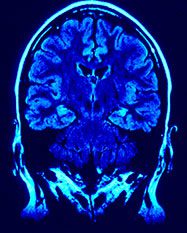

Stroke

Clayton County Fire and Emergency Services responded to over 300 stroke patients last year (2016). In 2008 Southern Regional Hospital became a Primary Stroke Center and in 2012 began its initial collaboration in addressing stroke care in the community with CCFES.

Every year about 800,000 people in the United States have a stroke. Stroke is the fifth leading cause of death in the United States and is the major cause of adult disability. Fact on average someone in the US dies every 4 minutes from having a stroke.

Stroke is a medical emergency. Do you know the signs of a stroke? Receiving immediate treatment is important in preventing death and disability from having a stroke.

By knowing the signs and symptoms of stroke, you can be prepared to take quick action and perhaps save a life—maybe even your own.

Signs of Stroke in Men and Women

- Sudden numbness or weakness in the face, arm, or leg, especially on one side of the body.

- Sudden confusion, trouble speaking, or difficulty understanding speech.

- Sudden trouble seeing in one or both eyes.

- Sudden trouble walking, dizziness, loss of balance, or lack of coordination.

- Sudden severe headache with no known cause.

Call 9-1-1 immediately if you or someone else has any of these symptoms.

Acting F.A.S.T. Is Key for Stroke

Acting F.A.S.T. can help stroke patients get the treatment they desperately need. The most effective stroke treatments are only available if the stroke is recognized and diagnosed within 3 hours of the first symptoms. Stroke patients may not be eligible for the most effective treatments if they don’t arrive at the hospital in time.

If you think someone may be having a stroke, act F.A.S.T. and do the following simple test:

F—Face: Ask the person to smile. Does one side of the face droop?

A—Arms: Ask the person to raise both arms. Does one arm drift downward?

S—Speech: Ask the person to repeat a simple phrase. Is their speech slurred or strange?

T—Time: If you observe any of these signs, call 9-1-1 immediately.